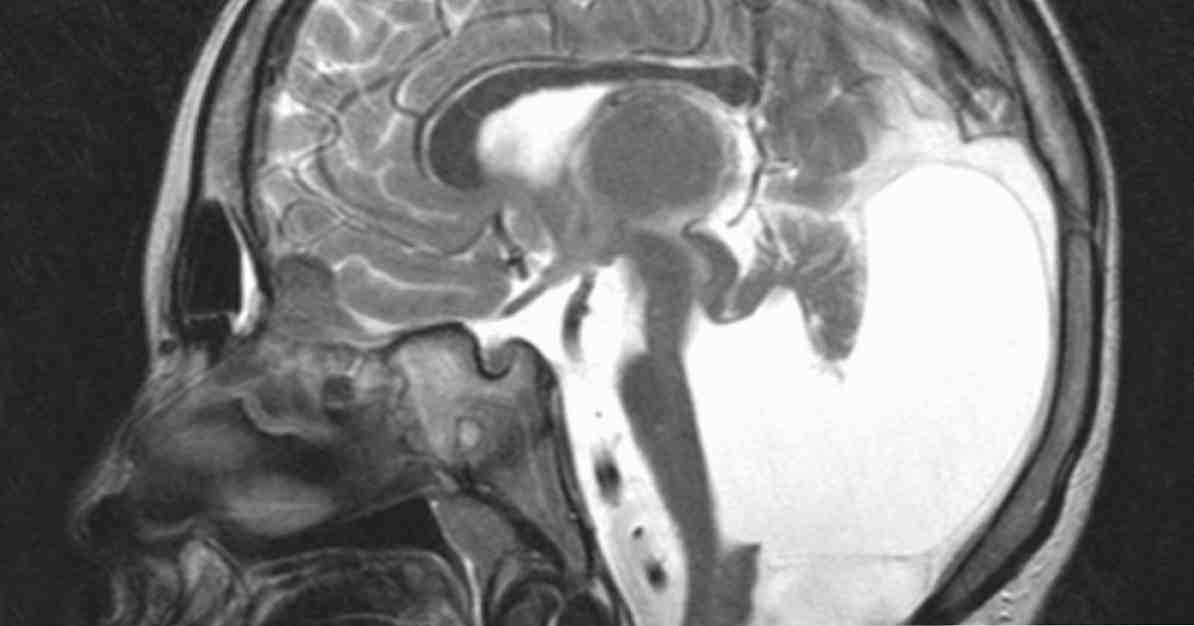

МРТ снимки мальформации Денди-Уокера